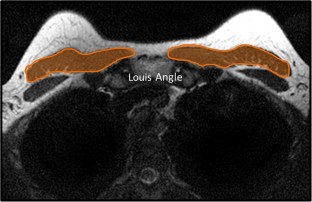

The retrospective study protocol was approved by our institutional review board. A total of n = 110 consecutive patients (mean age 56 ± 11 years) who were treated with neoadjuvant chemotherapy (NAC) for histologically proven primary breast cancer between January 2017 and January 2019 and in whom tumor response was checked with standard breast MRI were included. Two radiologists calculated the pectoralis muscle cross-sectional area before and after NAC.

Time between the MRI examinations, before starting NAC and after completing NAC, was 166.8 ± 50 days. PMA calculated pre-NAC (8.14 cm2) was larger than PMA calculated post-NAC (7.03 cm2) (p < 0.001). According to the Response Evaluation Criteria in Solid Tumors (RECIST) criteria, there were no significant differences between responders (complete or partial response) and non-responders (p = 0.362). The multivariate regression analysis did not show any significant relationships between ΔPMA and age, time between MRI exams, estrogen and progesterone receptor status, human epidermal growth factor receptor status (HER-2), Ki-67 expression, lymph node status, RECIST criteria, histological type, average lesion size, molecular categories, and grade. Inter-reader (k = 0.72) and intra-reader agreement (0.69 and 0.71) in PMA assessment were good.